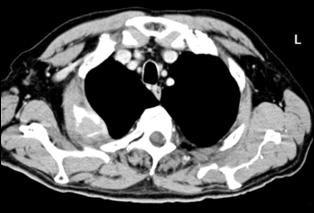

Cele mai multe metasteze la distanta, provocate de tumorile vezicale maligne, sunt localizate in plamani si in oase. Diagnosticul acestora se face prin: radiografii toraco-pulmonare, radiografii osoase sau scintigrame osoase (evidentiaza metastazele osoase cu 9-12 luni mai devreme decat expresia evidenta a acestora pe radiografiile standard).

4.5. Radiografia osoasa 4. Radiografia toraco-pulmonara

Figura 44. Metastaza in articulatia coxo-femurala

dreapta Figura 45. Metastaze pulmonare multiple dintr-un carcinom vezical

infiltrativ.

a. b.

Figura 4 Radiografie toraco-pulmonara cu metastaze pulmonare multiple

dintr-un carcinom vezical infiltrativ

Figura 47. Radiografie toraco-pulmonara cu metastaze pulmonare multiple dintr-un carcinom vezical infiltrativ.